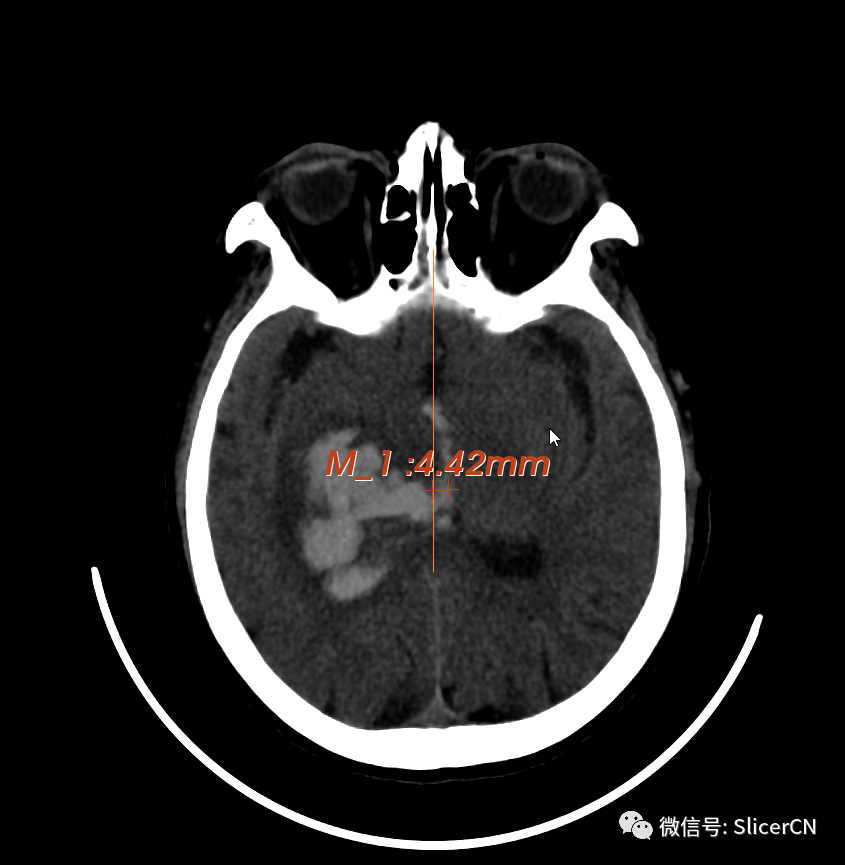

(神经影像数据可视化分析)

脑出血是神经内、外科最常见的疾病了,但关于它的一些问题,很难讲清楚。比如:

脑出血相关的问题很难,除了上帝,貌似只有数据能回答,而且是“大数据”。那么怎么了解数据?—— 当然是先看看长什么样咯!

一、特征数据的量化与获取